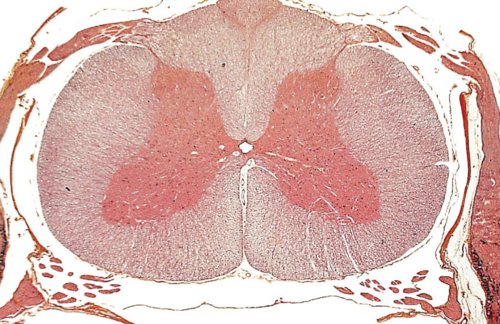

Anterior (ventral)

Posterior (dorsal)

gray horns

white columns

each side of the spinal cord has three funiculi (columns): dorsal (posterior) funiculus, lateral funiculus, and ventral (anterior) funiculus, which are further divided into tracts

anterior funiculi

floor of white column

lateral funiculi

middle of white column

posterior funiculi

ceiling of white columns

central canal

A tiny channel found within the spinal cord and inferior medulla oblongata

gray commissure

connects masses of gray matter; encloses central canal

white commissures

connects the white matter of the right and left sides of the spinal cord

anterior median fissure

a groove along the anterior midline of the spinal cord that incompletely divides it into symmetrical halves

posterior median sulcus

a shallow vertical groove dividing the spinal cord throughout its whole length in the midline posteriorly.